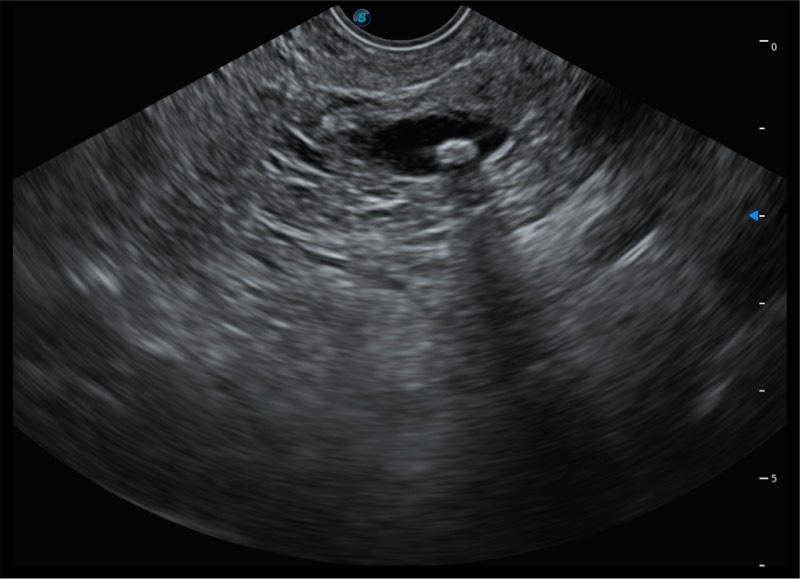

超声电子上消化道内窥镜

• 搭载百万级CMOS成像技术

• 及自主研发凸阵换能器,

• 可呈现优质的内镜和超声画面

基于二十年的超声技术积累,新葡的京集团8814检测站提供了最新一代的独立超声主机,在提供高质量图像的同时满足多学科使用。具备常见多普勒技术并提供弹性成像、声学造影等高端影像技术。新一代传感器具有更强的抗干扰能力并减少图像伪影。

• 150°超声扫描角度

• 4-12MHZ宽频输出